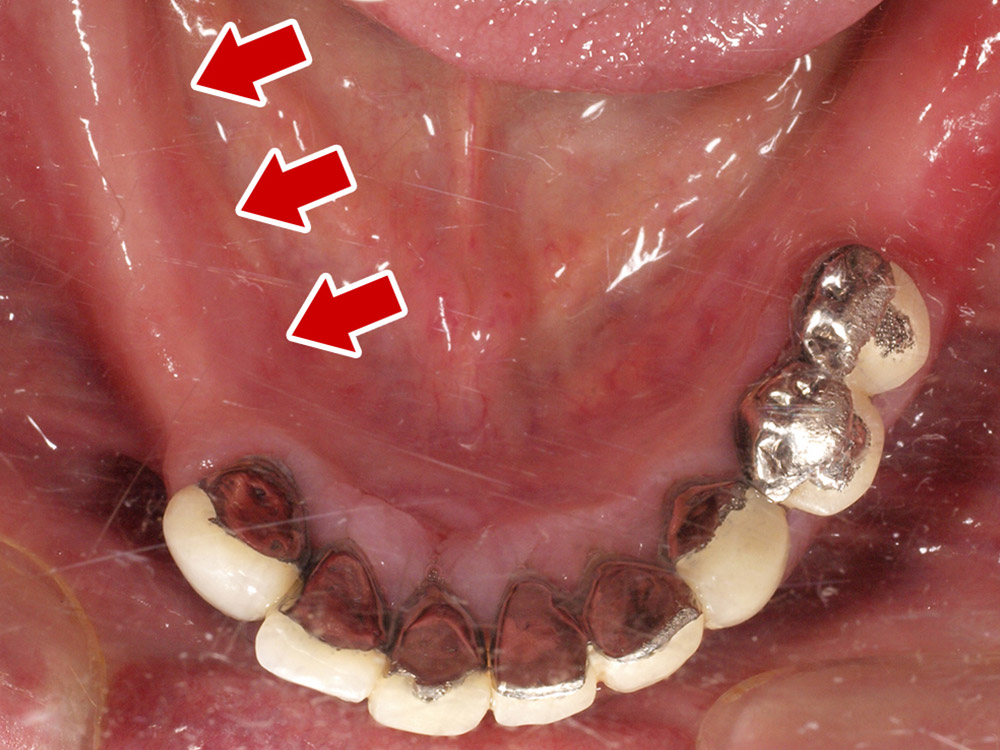

- 主訴

- 上顎入れ歯が辛い、下顎左右の歯が痛い、揺れる

- 処置内容

- 上顎6本(オールオン6) 下顎3本

- 治療費用

- 上顎:約350万円(税込)、下顎:約310万円(税込)仮歯まで5か月)

- 治療期間

- 上顎:1年(仮歯まで8か月)/約10回

下顎:8か月(仮歯まで5か月)/約7回

- リスク

- 上部構造物、仮歯の破折、術後の腫れ(3日)、人工歯根脱落リスクがあります